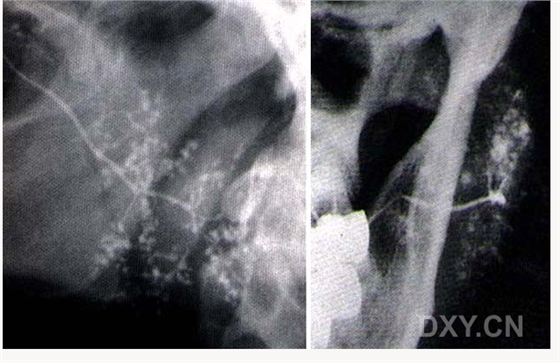

涎石病